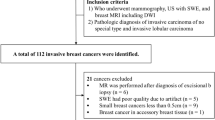

This study was performed on 6-to-8-week-old female C57BL/6J mice (Jackson Laboratory, Bar Harbor, ME, USA). Colon 38-luciferase-expressing tumor cells (2.5 × 104/5 μL) were mixed in a 1:1 ratio of Evans blue to Matrigel matrix (BD Bioscience, Mississauga, Canada). The tumor cells were injected orthotopically into the rectal wall as described by Uccello et al.16. Table 1 includes the number of tumors in each group, and the subsets of tumors excised on days 20 and 25 post-injection.

A total of 32 mice (27 tumor-bearing mice and five healthy mice (positive controls)) received SCRT. Fifteen additional tumor-bearing mice (negative controls) did not receive SCRT. Before treatment, two 4 mm titanium fiducial markers (Horizon, Teleflex, Morrisville, NC, USA) were placed on opposing sides of the rectal tumor to aid in CT-guided SCRT targeting as described in Uccello et al.16. A small animal radiation research platform (SARRP, Xstrahl Inc., Suwanee, GA, USA) with a 5 mm collimator was used to irradiate mice in the treated group with 5 Gy (Gy) from day 9 to 13 post-tumor cell injection.